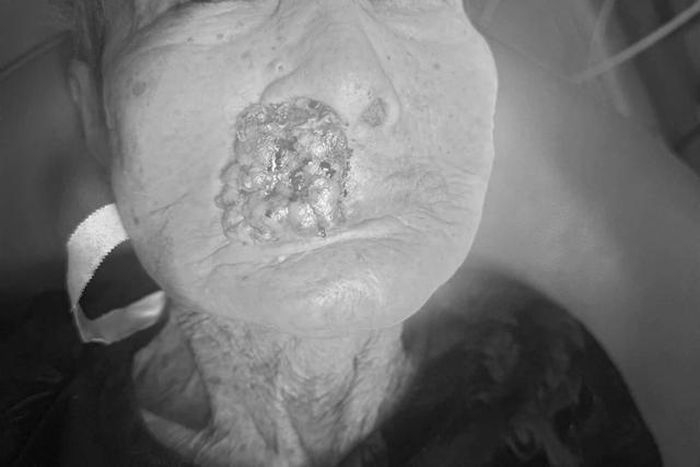

Ban đầu chỉ là nốt ruồi nhỏ trên mặt cụ bà 88 tuổi, sau 3 năm phát triển thành khối u ác tính, có giòi làm tổ khiến bệnh nhân đau đớn nhập viện.

Khi nhập viện, cụ Th. có một khối u lớn vùng môi trên, lở loét, chảy máu và rất nhiều giòi ký sinh bên trong khối u.

Thông tin trên Dân Trí, các bác sĩ khai thác tiền sử bệnh được biết cách đây 3 năm, cụ phát hiện một nốt ruồi nhỏ trên mặt nhưng không theo dõi hay điều trị. Nốt ruồi sau đó phát triển thành khối u ác tính, gây lở loét kéo dài, chảy máu và đau nhức dữ dội. Đến khi ổ loét nhiễm trùng nặng và có giòi xuất hiện, người nhà mới đưa cụ nhập viện.

Theo chẩn đoán ban đầu, bệnh nhân bị ung thư da tiến triển vùng môi, nghi biểu mô tế bào đáy. Biến chứng nhiễm trùng mô hoại tử, có giòi (myiasis). Sau khi hội chẩn liên chuyên khoa, các bác sĩ quyết định nhanh chóng phẫu thuật để loại bỏ ổ ký sinh trùng, kiểm soát nhiễm trùng, chảy máu và giảm đau đớn cho bệnh nhân.

Ca mổ cắt bỏ rộng khối u, làm sạch hoàn toàn ổ giòi, cầm máu và tạo vạt thẩm mỹ để đóng kín vết mổ. 3 ngày sau phẫu thuật, bệnh nhân giảm đau đớn rõ rệt, vết mổ khô, không nhiễm trùng. Cụ bà có thể ăn uống và sinh hoạt nhẹ nhàng trở lại.